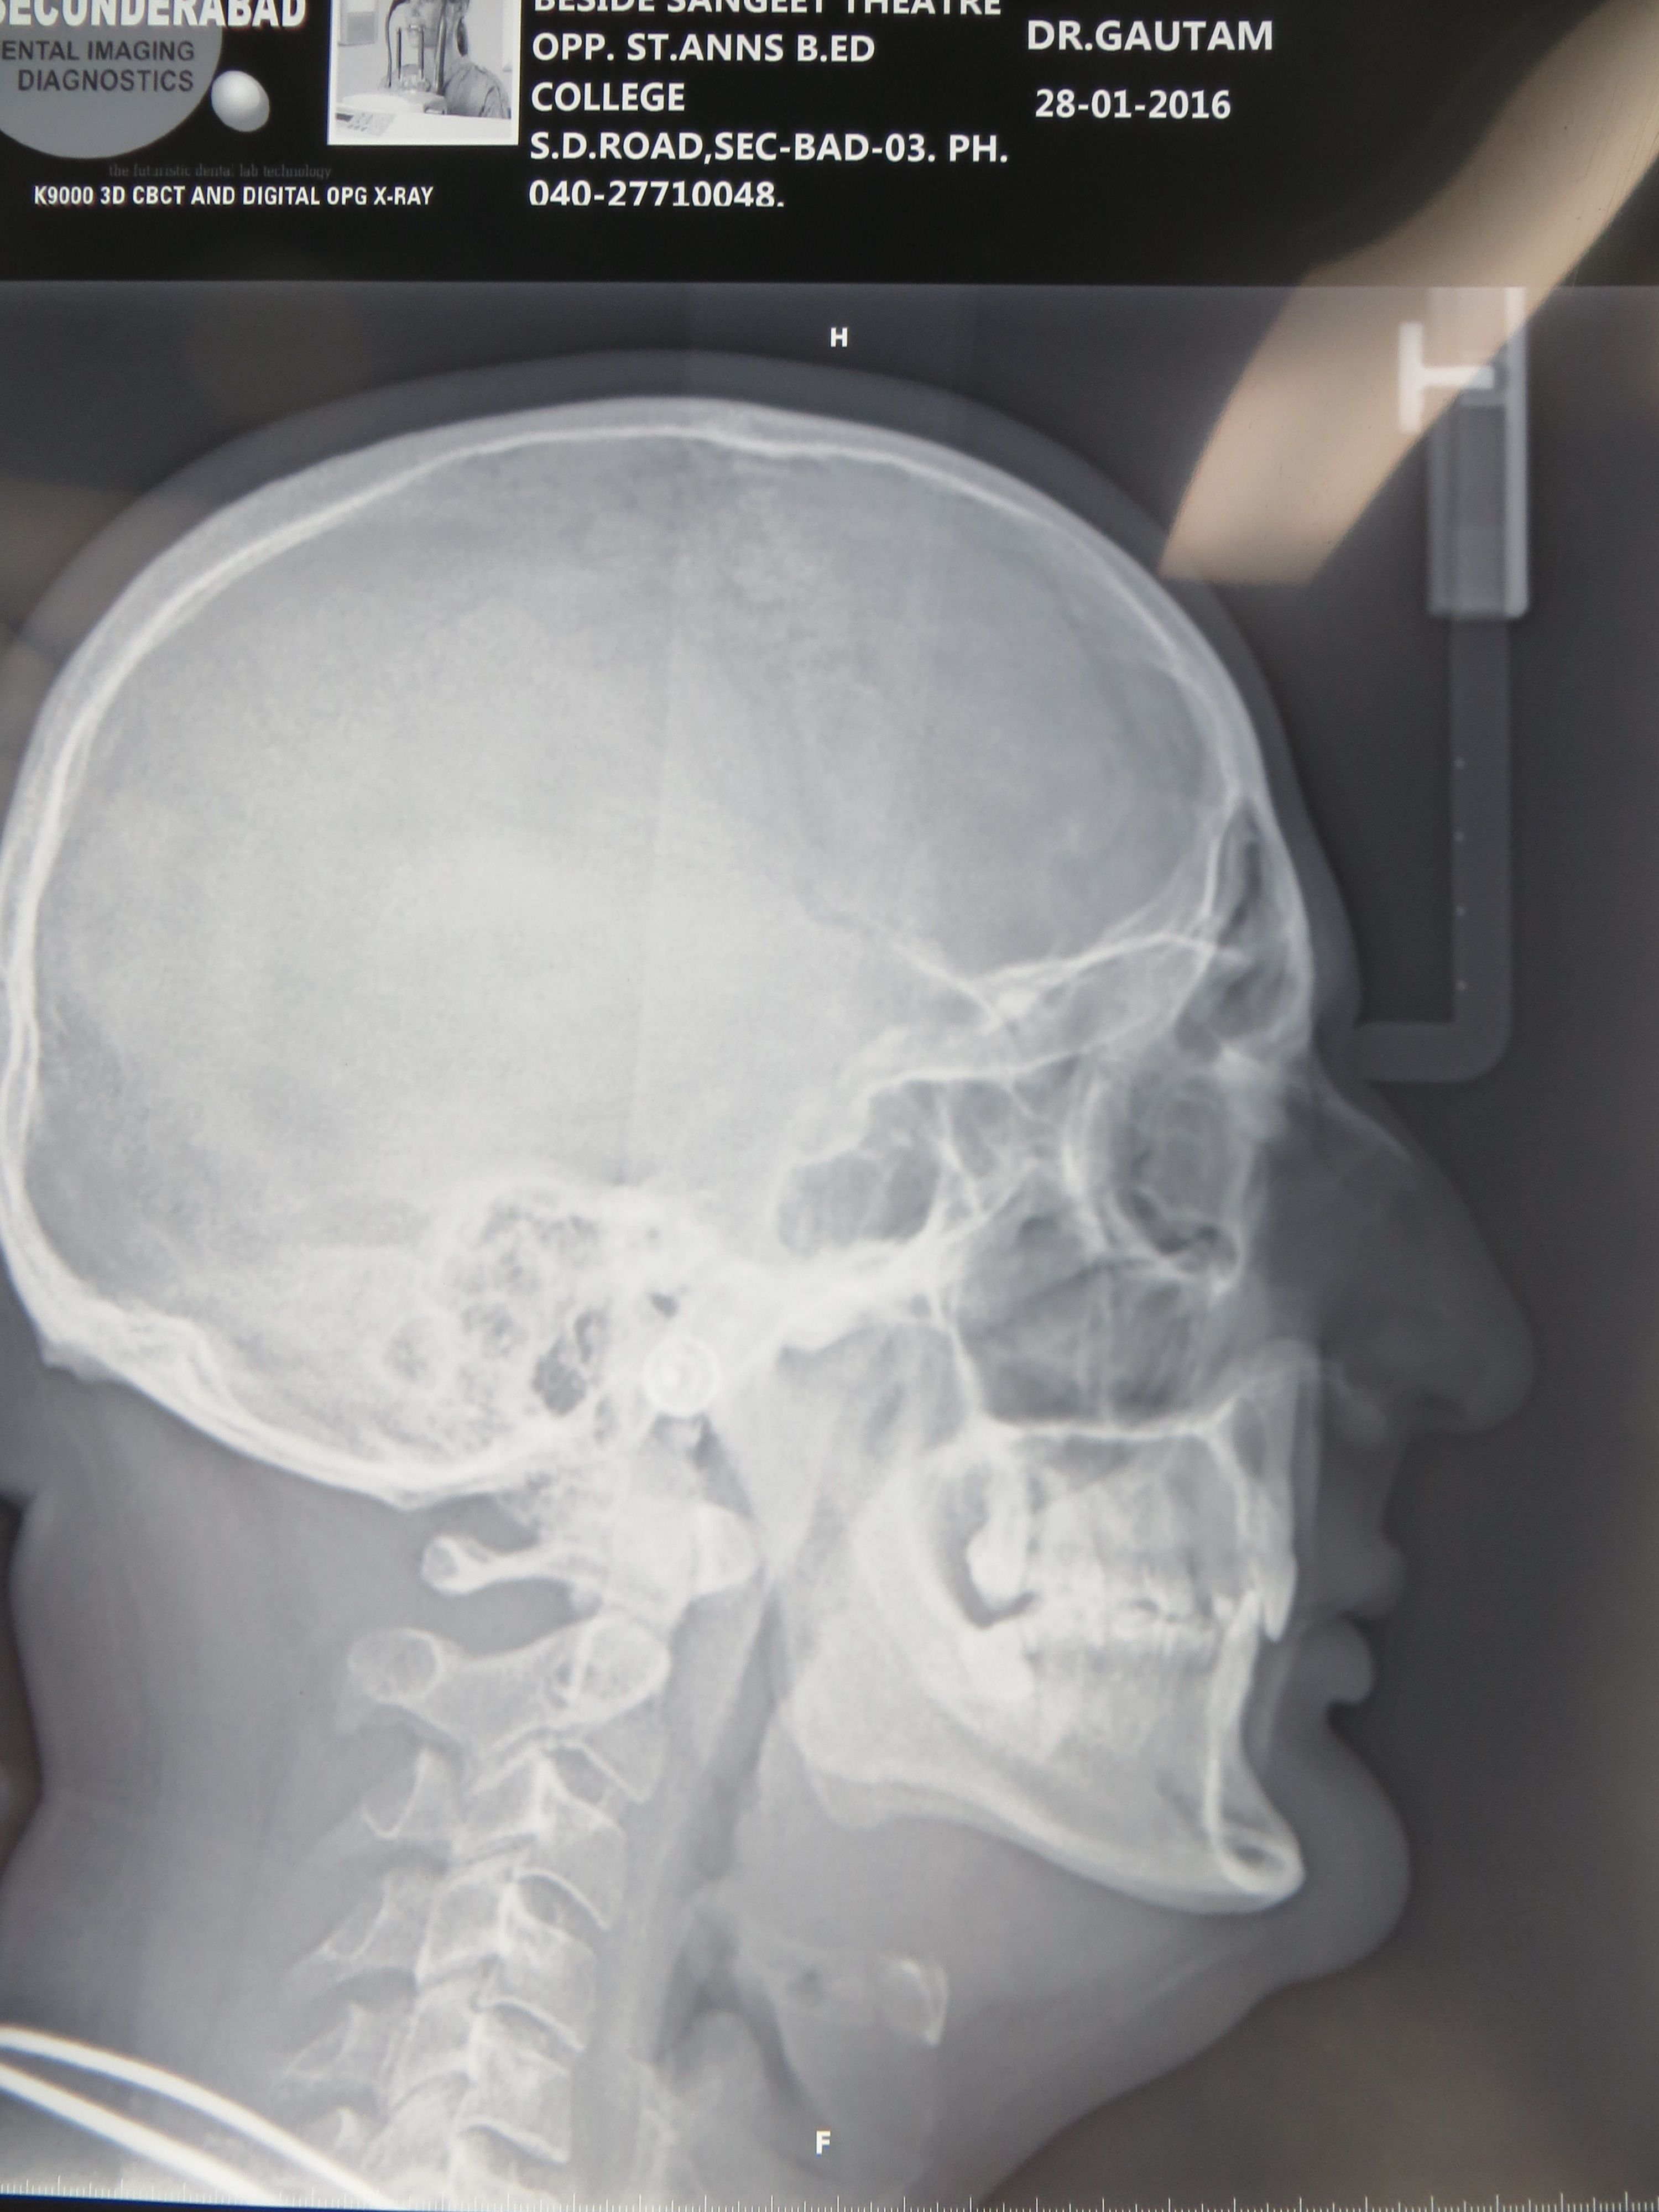

ORTHOGNATHIC AND COSMETIC SURGERY

Do you feel your jaws are not in alignment? Are your jaws very prominent or very retrusive? Do you want your chin to be more prominent? All these problems can be addressed with a proper assessment, xrays and corrective surgery. Improve your confidence and self esteem with cosmetic orthognathic surgery.